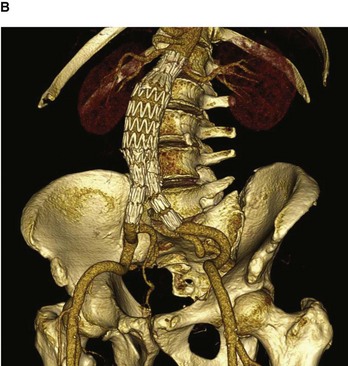

Abdominal aortic stent graft

An abdominal aortic aneurysm is a dilatation of the aorta and generally tends to occur in the infrarenal region (the region at or below the renal arteries). As the aorta expands, the risk of rupture increases, and it is now generally accepted that when an aneurysm reaches 5.5 cm or greater an operation will significantly benefit the patient.

With the aging population, the number of abdominal aortic aneurysms is increasing. Moreover, with the increasing use of imaging techniques a number of abdominal aortic aneurysms are identified in asymptomatic patients.

For many years the standard treatment for repair was an open operative technique, which involved a large incision from xiphoid process of the sternum to symphysis pubis and dissection of the aneurysm. The aneurysm was excised and a tubular woven graft was sewn into place. Recovery may take a number of days, even weeks, and most patients would be placed in the intensive care unit after the operation

Further developments and techniques have led to a new type of procedure being performed to treat abdominal aortic aneurysms—the endovascular graft. The idea of placing the graft into the aortic aneurysm and lining the dilated vessel is not new and was first described over 10 years ago. Since the original description the devices have been modified on a number of occasions (Fig. 4.149).

image image

Fig. 4.149 Volume-rendered reconstruction using multidetector computed tomography of patient with an infrarenal abdominal aortic aneurysm before (A) and after (B) endovascular aneurysm repair. Note the image only demonstrates the intraluminal contrast and not the entire vessel. White patches in the aorta (A) represent intramural calcium.

The technique involves surgically dissecting the femoral artery below the inguinal ligament. A small incision is made in the femoral artery and the pre-loaded compressed graft with metal support struts is passed on a large catheter into the abdominal aorta through the femoral artery. Using X-ray for guidance the graft is opened, lining the inside of the aorta. Limb attachments are made to the graft that extend into the common iliac vessels. This bifurcated tube device effectively excludes the abdominal aortic aneurysm.

This type of device is not suitable for all patients. Patients who receive this device do not need to go to the intensive care unit. Many patients leave hospital within 24–48 hours. Importantly, this device can be used for patients who were deemed unfit for open surgical repair.